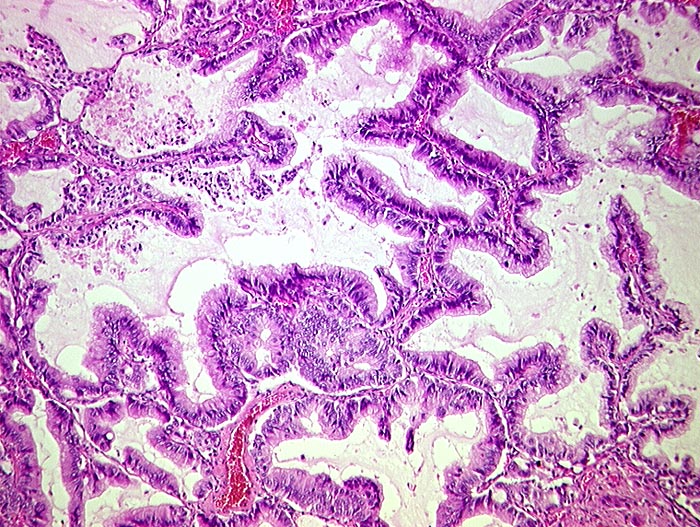

PathoPic ID 137 - muzinöses Bronchioloalveoläres Karzinom

muzinöses Bronchioloalveoläres Karzinom

Hochzylindrische schleimbildende Zellen mit geringen Atypien tapezieren die Alveolarsepten aus. Das Lungengerüst bleibt erhalten.

3cm grosser peripherer Lungentumor. Metastasen Lymphknoten,Hirn, Nebennieren.

Tumor bekannt seit 3 Jahren.